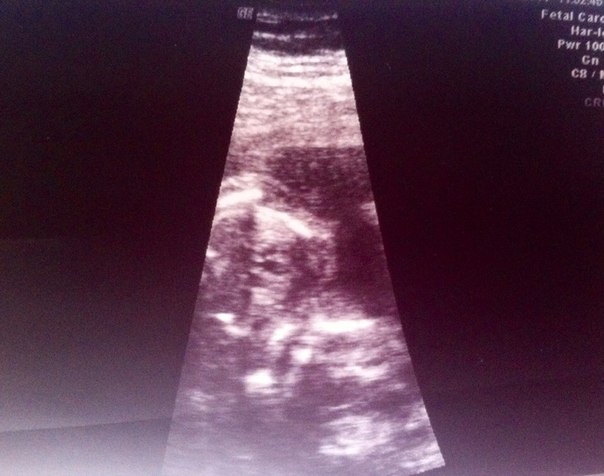

УЗИ 2 триместра ( 19+5)

Весим мы почти 300г. По развитию все хорошо, но поставили срок 19+1.

Подтвердили девчушку! Показали пирожок на экране!)) Будет у нас доченька!

Мадам наша все никак не хотела личиком поворачиваться. Вроде врач в режиме 2д увидел носик и ротик, сказал,что все в порядке, но в 3д поворота видимо недостаточно было..Ну да ладно, еще насмотримся на нашу малышульку

Вот напечатал "пирожок"

А вот здесь я мало что понимаю... вроде на профиль похоже...